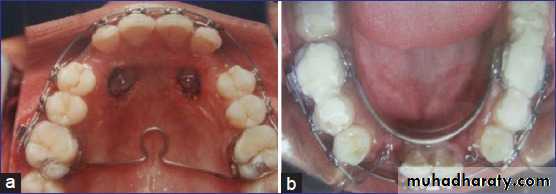

Surgical exposure with orthodontic treatment (palatal approach )

impaction